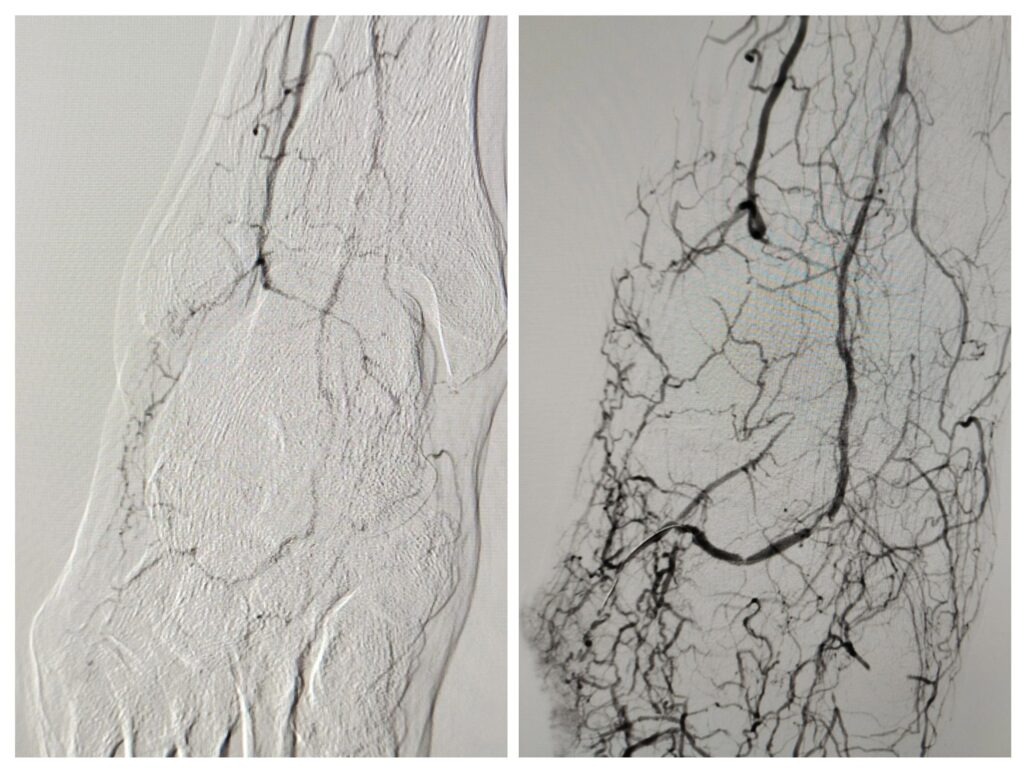

Siguiendo el principio de wound-related perfusion, se decidió realizar una arteriografía ipsilateral con intento de revascularización selectiva del territorio arterial directamente relacionado con la herida.

El objetivo fue mejorar el aporte sanguíneo específicamente hacia la zona lateral del pie, aumentando así el potencial de cicatrización y evitando una cirugía mayor o amputación.